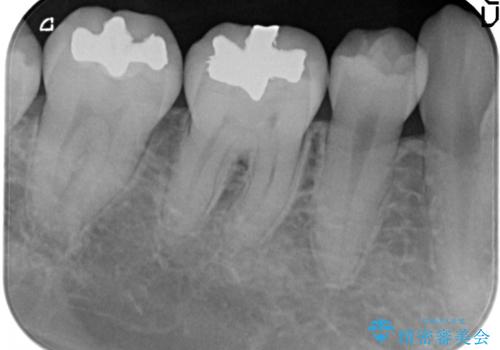

メタルインレーからセラミックインレーへ

- メタルインレーによる審美障害を主訴に来院されました。

セラミックインレーに治療を行っております。

e-max プレスインレーにて修復治療を行っているため適合性及び審美性の高い治療を行うことができます